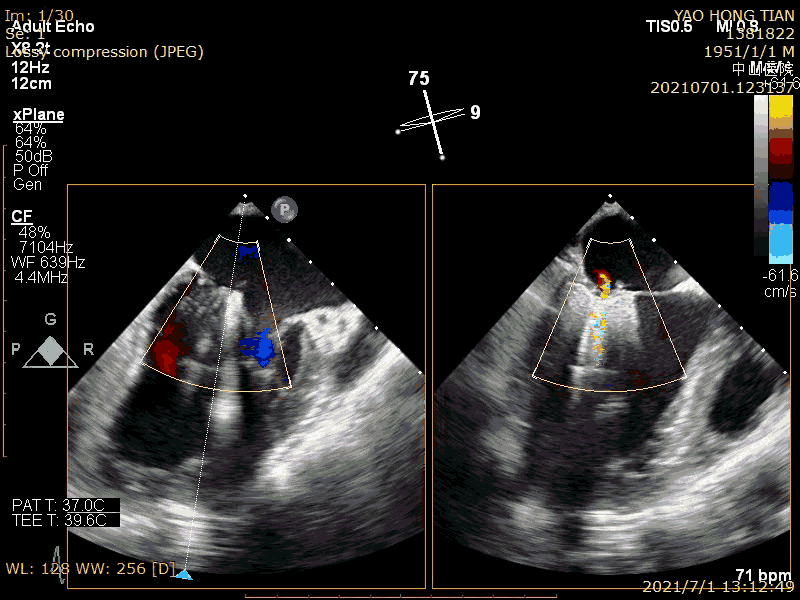

完全夹合评估效果

最后效果(轻微反流),最大/平均压:差4/1mmHg

在二尖瓣反流病因构成中,功能性反流更常见,其为器质性反流的3-4倍(Am Heart J. 2018 ;203:39-48.)。而房性功能性二尖瓣反流(AFMR),在功能性反流里也是非常常见,笔者估测可占到40%。本例结果显示ValveClamp 对AFMR效果良好,操作简便,导管操作时间不到20分钟,总手术时间不到50分钟,术后轻微反流。特别提到的是,本例反流范围达13mm,且反流为多束。一个夹子ValveClamp即起到完美效果,而其他产品很可能需要2-3个夹子,这充分体现了ValveClamp“以小治大” 的设计优点。仅使用单个夹子,可以降低手术难度和手术时间,降低耗材成本。